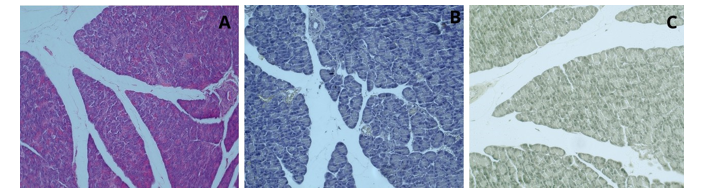

Following the hematoxylin and eosin staining procedure, examination of the liver tissue under a light microscope revealed that the histological structures appeared in their characteristic colors; the cell nuclei were observed in purple, and the cytoplasm appeared pink. As a result of the examination of the pancreas tissue, the histological structures were observed in their typical colors. The cell nuclei appeared blue-purple, the cytoplasm was pink, and the sinus acini and Langerhans islets were clearly distinguished. Examination of the spleen tissue showed that the histological structures were also observed in their characteristic colors. The cell nuclei were blue-purple, cytoplasm was pink, pulp was white, pulp was red, and trabecular structures were clearly detected (Figure 1).

Figure 1: Liver (A), Pancreas (B) and Spleen Tissue (C); (H&E; x20)